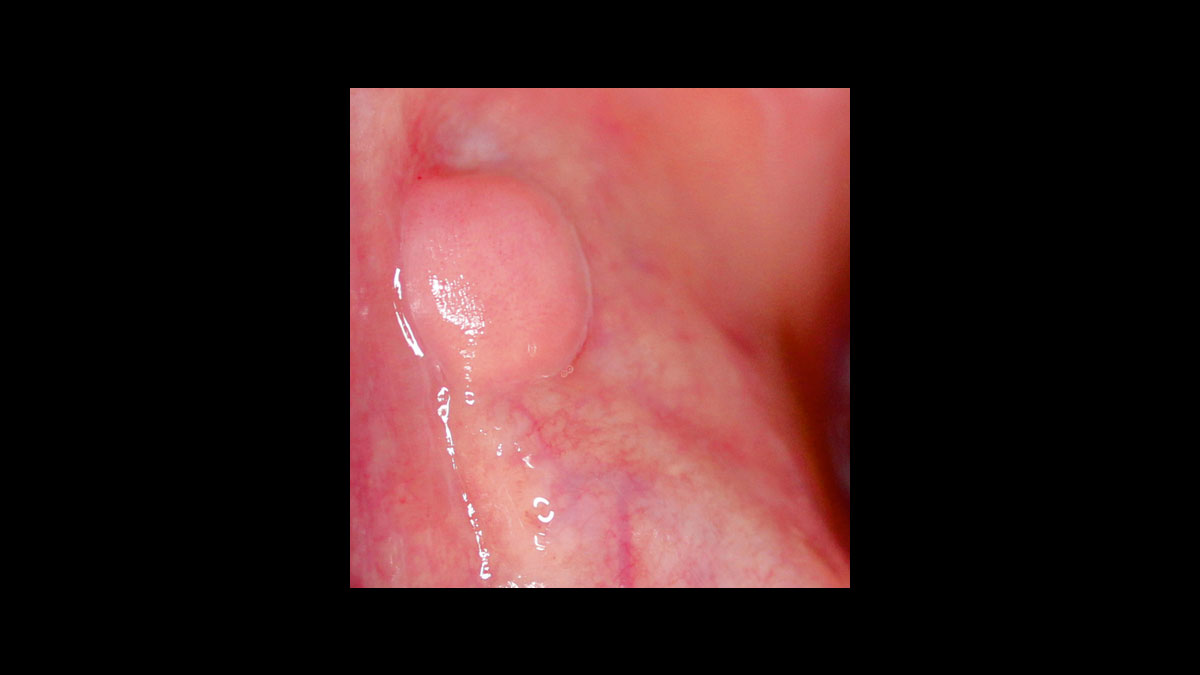

• Épulis

• Fibroma

Fibroma

Frenectomía